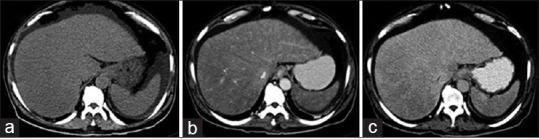

Esophagogastroduodenoscopy showed Grade-2 esophageal varices with gastropathy and duodenopathy. Computerized tomography (CT) abdomen with contrast [Figure 1], showed hepatomegaly with heterogeneous hepatic parenchymal enhancement with areas of hypodense areas in portal venous phase, homogenizing on delayed images (3 min); nonopacification of the right, middle, and left hepatic veins. Splenomegaly with moderate ascites. The diagnosis of Budd–Chiari syndrome was considered.

| Figure 1:(a) Plain computerized tomography scan showing hepatosplenomegaly with ascites, (b) arterial phase showing heterogeneous hepatic parenchymal enhancement, (c) venous phase showing areas of hypodense nonenhancing areas in the right lobe of liver with nonopacification of hepatic veins (right, middle, and left) draining into inferior vena cava

Radiological findings of hepatic amyloidosis are nonspecific. Ultrasound may show heterogeneous or coarse parenchymal echotexture. Unenhanced CT shows enlarged liver with heterogeneously decreased parenchymal attenuation.[9,16] Parenchymal calcifications are rarely described. On contrast enhanced CT, areas of amyloid infiltration appear as focal hypoattenuating areas, with subsequent contrast filling of these areas in delayed images. The findings are probably due to impaired blood flow as a result of amyloid infiltration of blood vessel walls and hepatocyte congestion.